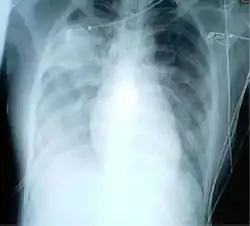

![]() Patología de un tejido pulmonar debido al SARS | ||

Un caso probable se define como un caso sospechoso con el hallazgo adicional de neumonía o síndrome respiratorio por radiografía de tórax o autopsia.